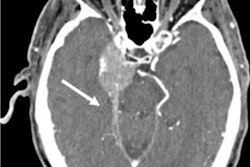

PCCT's ability to produce high-quality images at lower radiation doses compared to conventional CT could lead to better patient care, said Dr. Dominik Juskanic of the National Cancer Institute Slovakia in Bratislava.

"[PCCT technology means] it's safe to go low dose in chest imaging and opens doors to CT-based cancer screening, [as well as conditions such as] connective tissue disease-associated interstitial lung disease and long COVID screening," he said.